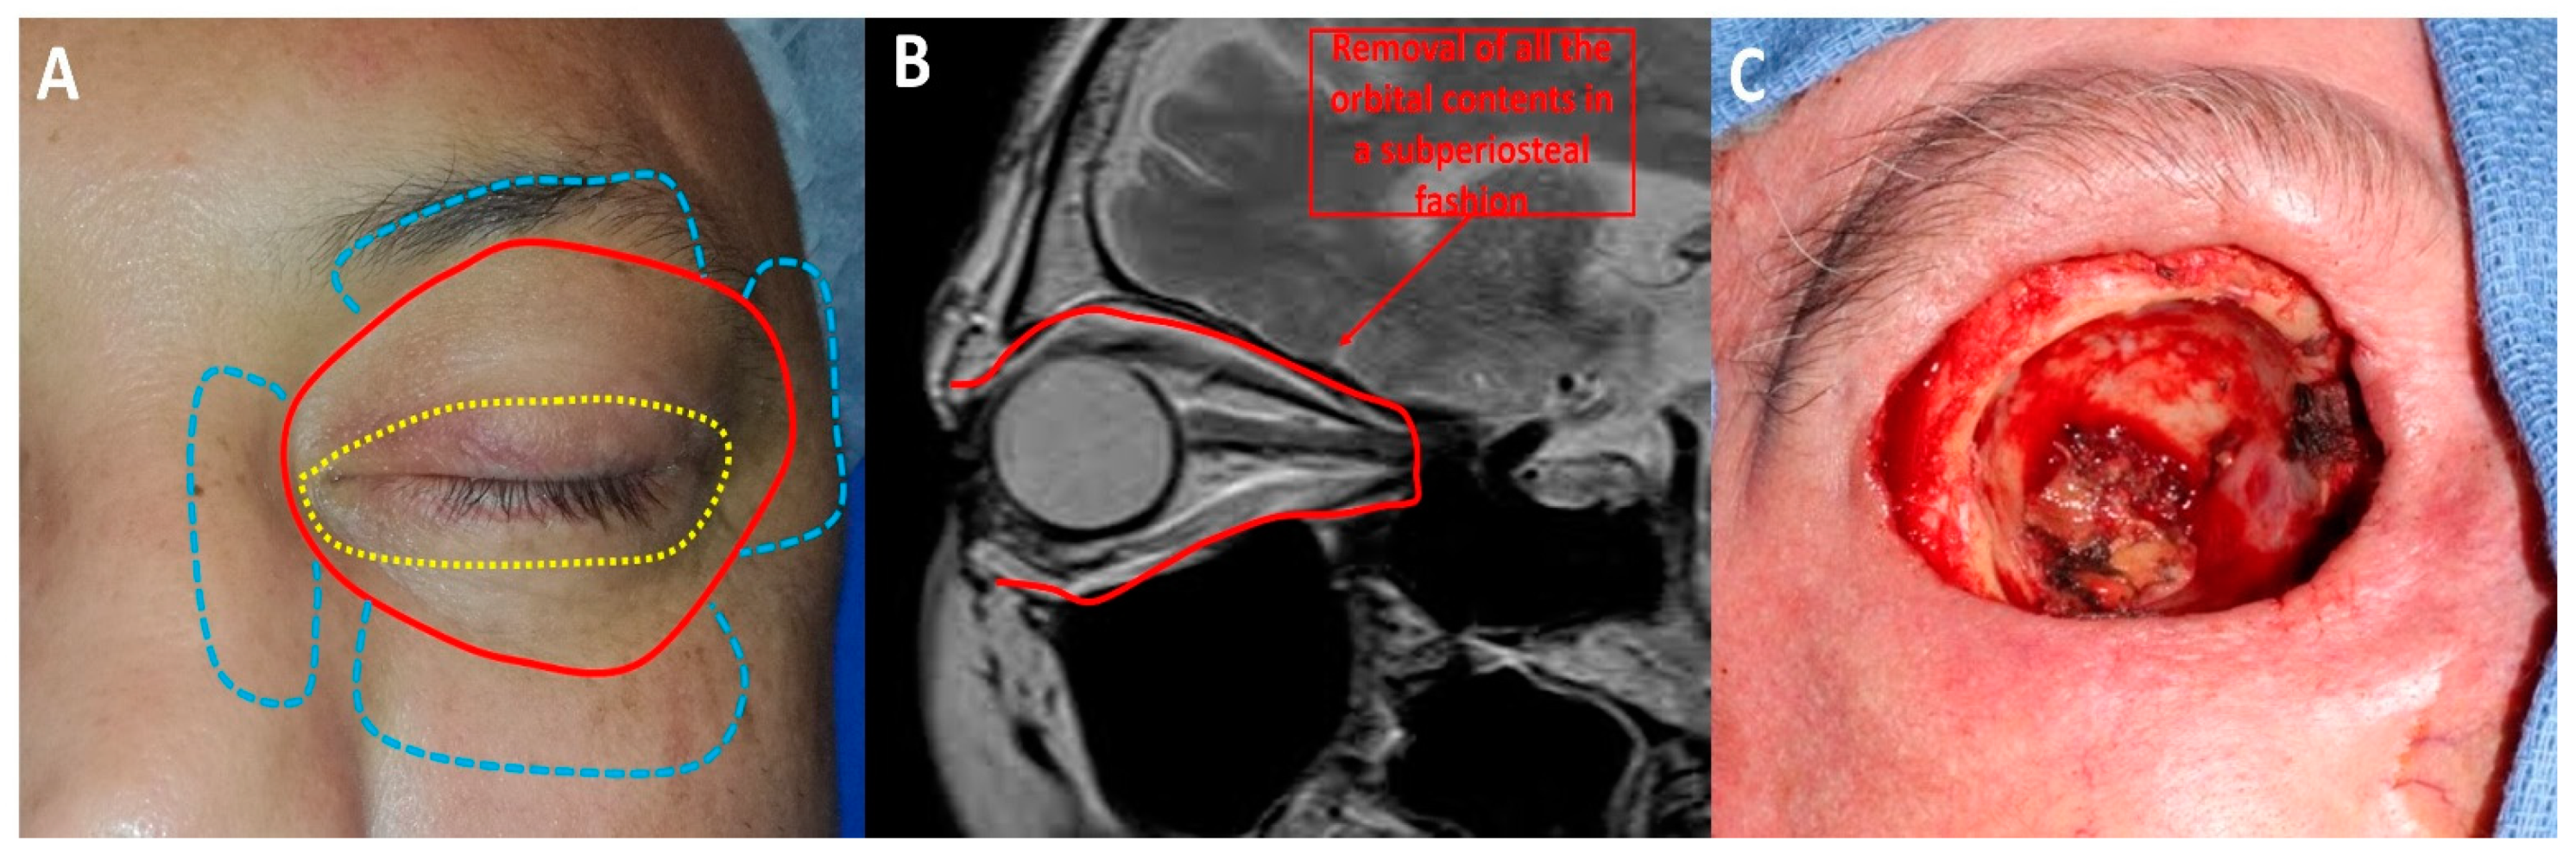

OE is a radical surgical procedure consisting of the removal of the entire orbital contents, including the eye and oculomotor muscles, in a subperiosteal fashion (Figure 2) [5]. Historically, OE was first described in 1583 by Bartisch et al. [6]. Depending on the tumour location and extent, OE may be enlarged to the adjacent sinus cavities or anterior cranial fossa. Reconstruction differs depending on the surgeon’s speciality and ranges from spontaneous granulation of the orbital socket to more complex and time-consuming free flaps [7]. Cosmetic rehabilitation is better achieved with an orbital prosthesis retained by orbital implants, skin glue or glasses [4]. Cosmetic rehabilitation depends on orbital socket healing and is often delayed, especially in the case of orbital implant placement [5]. Although recent progress has been made in terms of reconstructive strategies and cosmetic rehabilitation [4], OE is associated with anxiety and depression [8]. Periocular eyelid malignant tumours invading the orbit are the most common indication for OE [9]. BCC is one of the most common eyelid malignant tumours invading the orbit. Although BCC virtually does not metastasise, it is associated with local aggressiveness, as shown in Figure 3. Other potential metastatic malignant tumours, such as SCC, melanoma or lacrimal gland tumours, often require OE. To date, no studies with a high level of evidence have shown the benefit of OE compared with conservative surgery in terms of overall survival [4]. The advantages and disadvantages of OE are shown in Figure 4.

Figure 2.

Orbital exenteration: (A) Several techniques have been described: eyelid-sparing orbital exenteration (yellow), total orbital exenteration (red) and orbital exenteration extended to surrounding orbital structures (blue). (B) Orbital exenteration consists of removing all the orbital contents. (C) Intraoperative photograph of a case of total orbital exenteration.